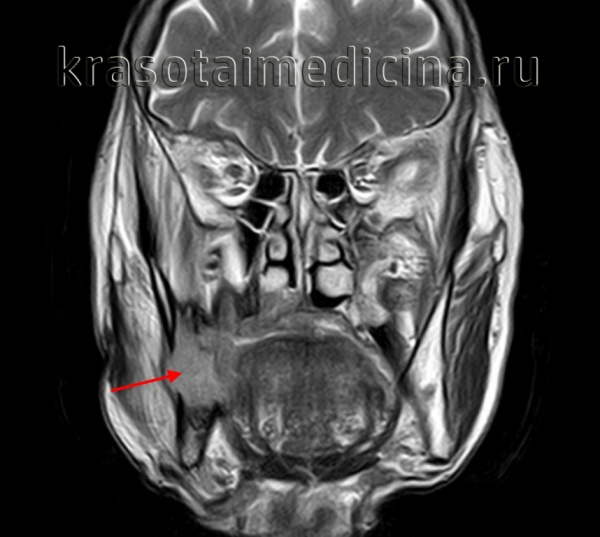

(Слева) На аксиальной МРТ (Т1ВИ) в глубокой доле левой околоушной железы визуализируется грушевидное объемное образование с промежуточным сигналом. Окологлоточный жир смещен кпереди и кнутри. Отсутствует жировая пластинка между опухолью и глубокой долей околоушной железы, что свидетельствует об истинной интрапаротидной ДСО.

• Абсолютно необходимо отличать ДСО глубокой доли околоушной железы от истинной окологлоточной ДСО:

о Ищите жировую пластинку между тканью околоушной железы и ДСО